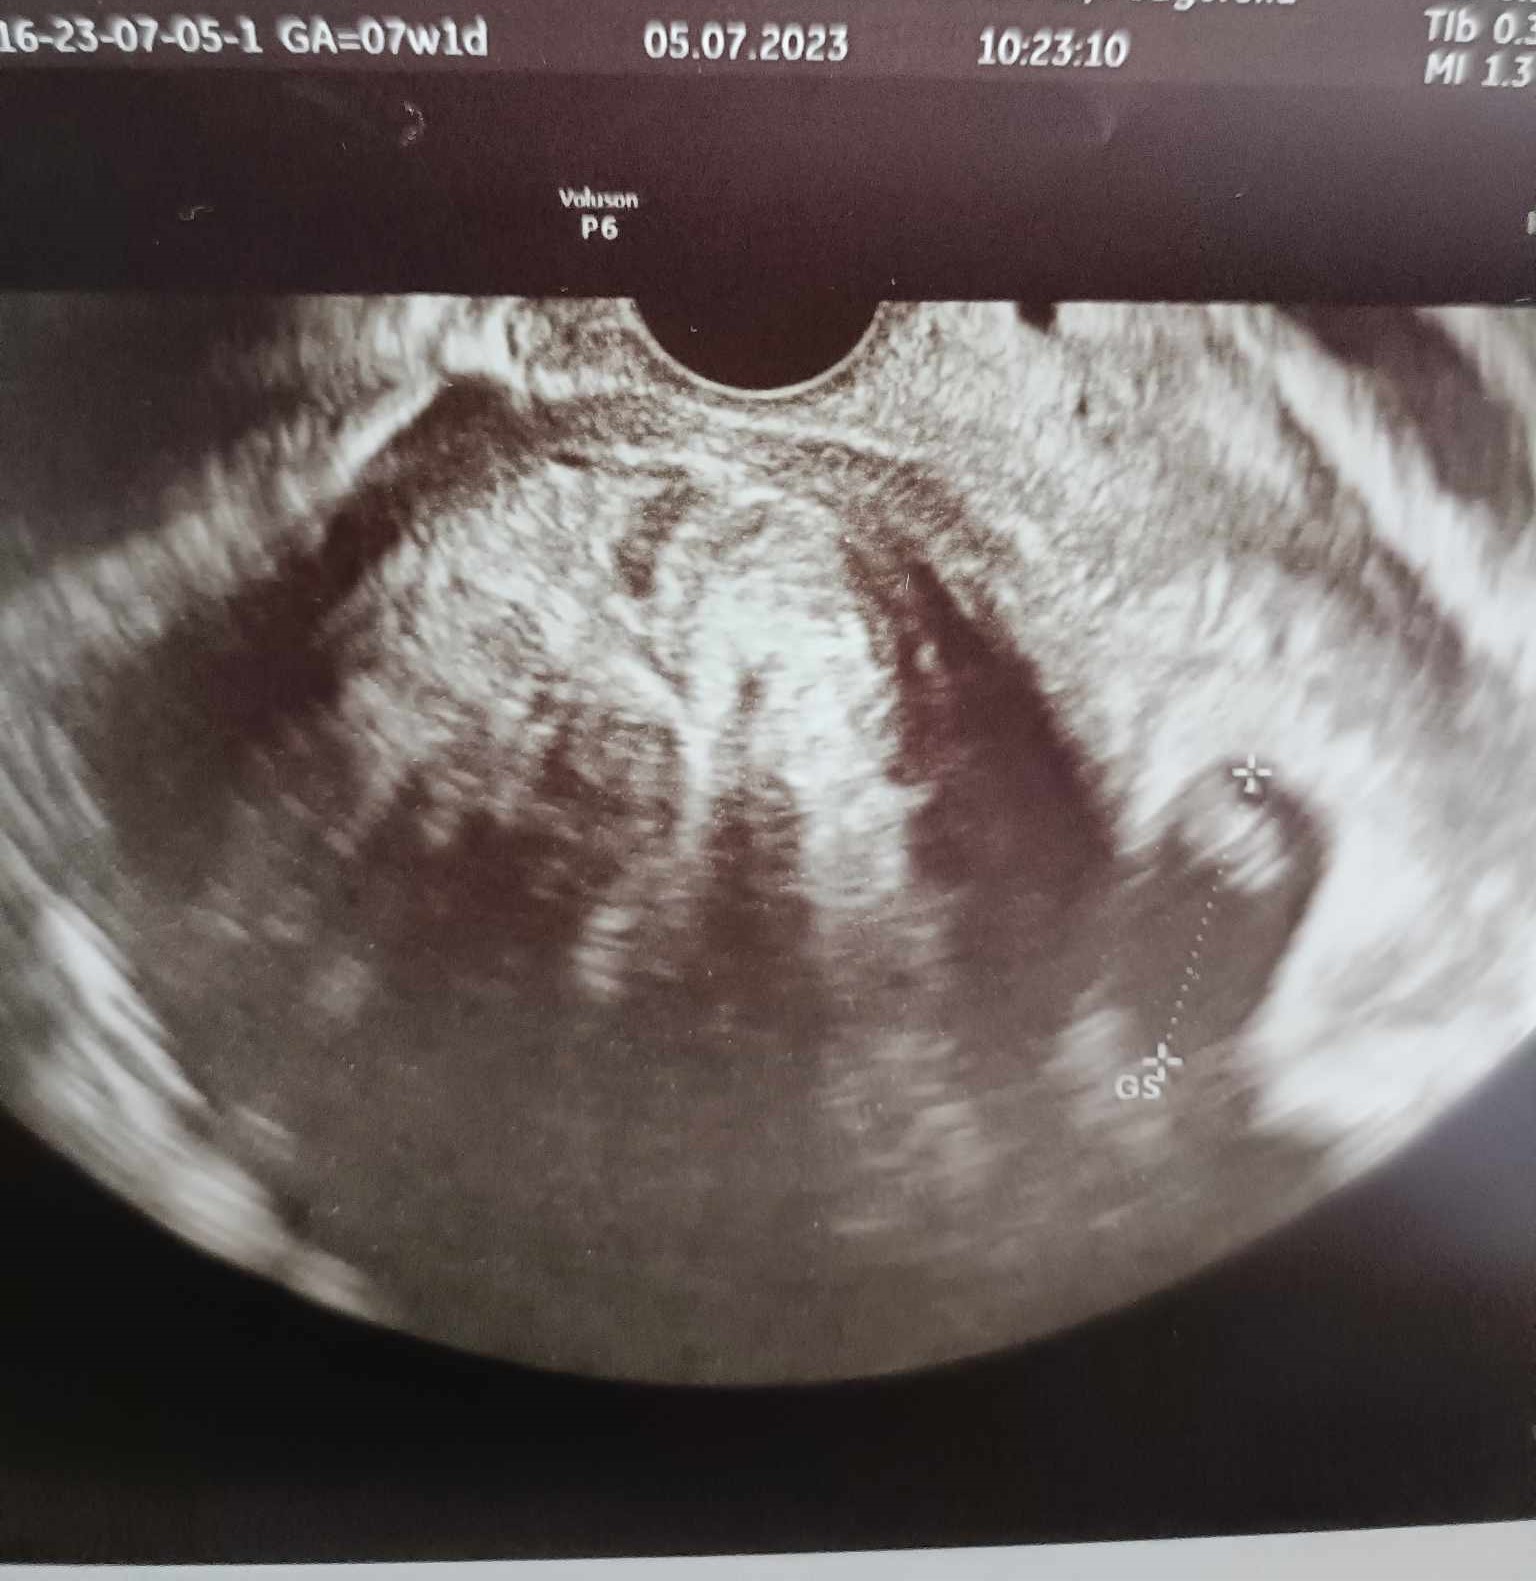

Melduję się i ja. Jak to określiła lekarka, mój zawodnik ma już cały centymetr, a serce bije jak dzwon. Termin z om idealnie pasuje do usg, 7w1d. Tyle, że jest problem, bo bardzo urosły mięśniaki. Największy na ten moment ma 7,5cm i zepchnął kropka (widać na zdjęciu, mały kropek po prawej stronie, a ta duża kula na środku to mięśniak) :( Przez to obraz na usg też był bardzo niewyraźny. Mimo braku miejsc lekarka wpisała mnie na przyszyły piątek, zostanie dłużej w pracy i będę miała zrobione kolejne usg na innym aparacie. Z zaleceń na teraz to dostałam skierowanie na badania, muszę pójść do endokrynologa, ze względu na IO. Czy któraś z was też ma? Jestem pod opieką psychodietetyka i od kilku miesięcy byłam na redukcji, bez leków. Chciałam najpierw spróbować samą dietą i ćwiczeniami. Wracając do ciąży, to na kolejnej wizycie założy mi kartę i da skierowanie na oddział patologii ciąży, żebym równocześnie była też u nich pod obserwacją. Także następna wizyta 14.07, badania prenatalne 9.08, a termin porodu 20.02 :)